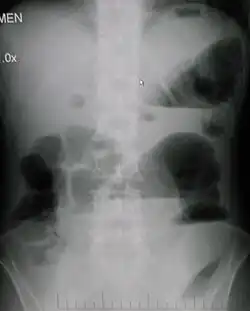

Upright abdominal X-ray demonstrating a small bowel obstruction. Note multiple air fluid levels.